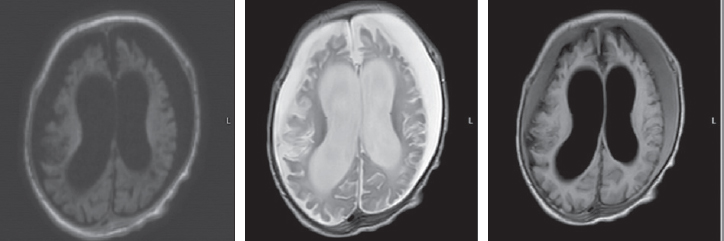

The differential diagnosis of paroxysmal conditions, as well as disorders of muscle tone (hypertension) in the neonatal period and in young children is quite complicated. Various states of the nervous system in newborns are transient and permanent, optimal and suboptimal, normal and pathological. Among them, we can mention non-epileptic paroxysmal states of early childhood. In some cases, non-epileptic paroxysmal states of early childhood is accompanied by motor disorders, manifested by an excessive increase in limb tone in newborns. This pathological condition of muscle tone in the English-language literature is referred to by the term stiffness baby (the syndrome of a “rigid” or “fettered” baby). Neonatal pathological muscle hypertonicity, unlike physiological hypertonicity of muscles of a newborn, is a rather rare condition. The article presents literature data and a description of the clinical observation of a patient with hyperekplexia. Hyperekplexia is a rare paroxysmal movement disorder in young children. The main clinical variants of the disease, methods of diagnosis and correction, the main mutations associated with this condition are considered. The article describes the own clinical observation of an early-age patient with hyperekplexia, its clinical picture, features of paroxysmal states and therapy, neuroimaging data, electroencephalographic phenomena recorded in the patient and genetic testing that confirmed the diagnosis of non-epileptic paroxysmal disorders. The child has a mutation in the ATAD1 gene associated with type 4 Hyperekplexia (618011).